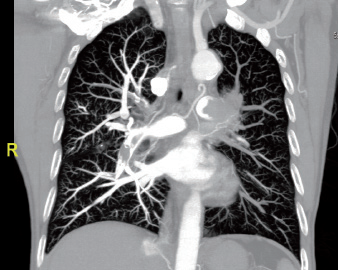

Blood Clots

CT scans are essential for rapidly detecting blood clots in critical areas such as the lungs (pulmonary embolism), brain (acute stroke), and deep veins (deep vein thrombosis). They